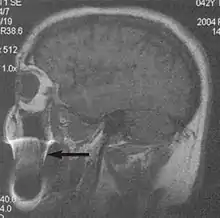

Metal artifacts occur at interfaces of tissues with different magnetic susceptibilities, which cause local magnetic fields to distort the external magnetic field. This distortion changes the precession frequency in the tissue leading to spatial mismapping of information. The degree of distortion depends on the type of metal (stainless steel having a greater distorting effect than titanium alloy), the type of interface (most striking effect at soft tissue-metal interfaces), pulse sequence and imaging parameters. Metal artifacts are caused by external ferromagnetics such as cobalt containing make-up, internal ferromagnetics such as surgical clips, spinal hardware and other orthopaedic devices, and in some cases, metallic objects swallowed by people with pica.[3] Manifestation of these artifacts is variable, including total signal loss, peripheral high signal and image distortion (Figs 3 and 4).[1] Reduction of these artifacts can be attempted by orientating the long axis of an implant or device parallel to the long axis of the external magnetic field, possible with mobile extremity imaging and an open magnet. Further methods used are choosing the appropriate frequency encoding direction, since metal artifacts are most pronounced in this direction, using smaller voxel sizes, fast imaging sequences, increased readout bandwidth and avoiding gradient-echo imaging when metal is present. A technique called MARS (metal artifact reduction sequence) applies an additional gradient, along the slice select gradient at the time the frequency encoding gradient is applied. ==Signal processing dependent artifacts== The ways in which the data are sampled, processed and mapped out on the image matrix manifest these artifacts.[1]